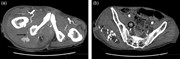

Delayed iliacus compartment syndrome following femoral artery puncture: case report and literature review

Bibombe P. Mwipatayi and others

Journal of Surgical Case Reports, Volume 2016, Issue 6, June 2016, rjw102, https://doi.org/10.1093/jscr/rjw102